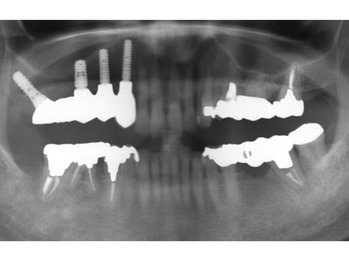

さっそく レントゲンからみてみましょう。

上顎右側(向かって左手です)が欠損しています。

患者様はインプラント治療をご希望されています。

欠損部には、骨吸収が認められます。

もう一症例みてみましょう。

上顎に多くの欠損が認められます。

多くの欠損がある場合、全ての欠損部にインプラントが必要なわけではありません。

今回の治療でも5本のインプラントを埋め込み、

8歯分の被せ物を作製するインプラントブリッジで対応しました。